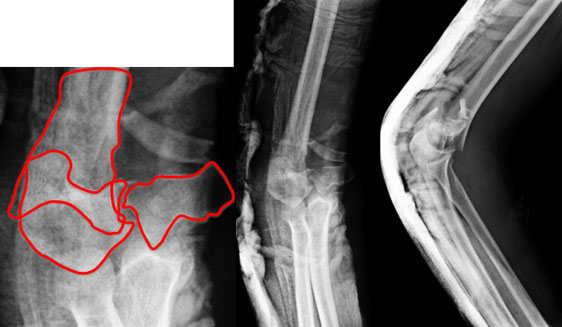

Comminuted Fracture Distal Humerus

| At Presentation |

| A 67 year old gentleman had a fall on the elbow and presented with fracture of distal end of humerus (lower portion forming part of the elbow joint). The fracture was extending into the articular portion of the humerus. This was complicated by the complex nature of the fracture as the bone was broken into many pieces –the larger fragments demarcated by red lines. |